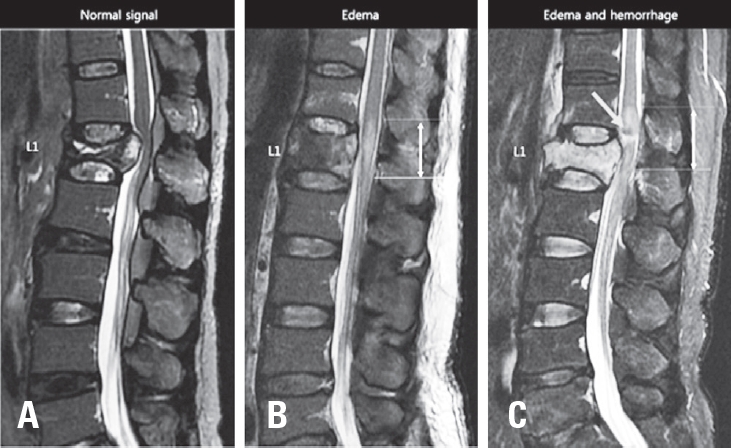

We performed retrospective cohort study evaluating 40 patients who presented to a level I trauma center between 2004 and 2017 with acute T-CMS and undergone a spinal surgical procedure. Diagnosis of T-CMS was made if all three criteria were met: (1) acute traumatic vertebral fracture in T12, L1, or L2; (2) the presence any neurologic deficit regarding CMS including leg weakness, decreased voluntary anal contraction, or sensory change in lower extremity or perianal area; (3) compression of CM or intramedullary signal change in CM on T2-weighted MRI (Fig. 1). The location of conus medullaris was confirmed on T1 and T2-weighted sagittal and axial images. Cases with compression of cauda equina (n=4) or compression or signal change in thoracic spinal cord (n=1) without involvement of CM were excluded.

T2 weighted mid-sagittal MRI scans at acute injury were collected for each patient. MRI mid-sagittal image was defined as a sagittally oriented image in which the spinous processes were best visible. Three categories of intramedullary signal in CM were determined according to the presence of intramedullary edema or hemorrhage (Fig. 2). Type I is normal without signal change in CM. Type 2 is intramedullary edema in CM, which had intramedullary lesions of high signal intensity on T2-weighted image. Type 3 is mixed intramedullary edema and hemorrhage in CM. Intramedullary hemorrhage present with low signal intensity on T2-weighted image. Maximal vertical length of intramedullary edema in CM was measured on T2-weighted sagittal image. Maximal canal compromise at mid-sagittal image was determined by measuring anteroposterior (AP) canal diameter at the point of maximal canal compromise. Maximal AP canal encroachment ratio was calculated using AP canal diameters of fractured vertebra (DF) and one level above (DA) and below (DB) vertebra; maximal osseous canal compromise=[1-DF/{(DA+DB)/2}]×100%. All radiological measurements were done by one experienced surgeon who was blinded to neurological outcome of patients and done by picture archiving and communication system (INFINITT PACS; INFINITT, Seoul, Korea).

Fig. 1.

Diagnosis of acute traumatic conus medullaris syndrome on T2 weighted mid-sagittal MR image. (A) MR image of spinal cord injury showing acute vertebral fractures in T12, L1, and L2 with T2 hyperintensity on spinal cord without the involvement of conus medullaris. (B) MR image of conus medullaris syndrome showing acute vertebra fractures in T12 and L1 with T2 hyperintensity on conus medullaris. (C) MR image of cauda equine syndrome showing acute vertebral fracture in L2 with no involvement of conus medullaris. Bidirectional arrow represent whole length o conus medullaris.

Signal characteristics in conus medullaris of MR image. (A) Type I: MR image of simple compression of conus medullaris without signal change in conus medullaris. (B) Type II: MR image of intramedullary edema in conus medullaris manifesting as T2 hyperintensity on conus medullaris (white arrow). (C) Type III: MR image of intramedullary edema and hemorrhage manifesting as T2 hypointensity (grey arrow) surrounded by T2 hyperintensity.